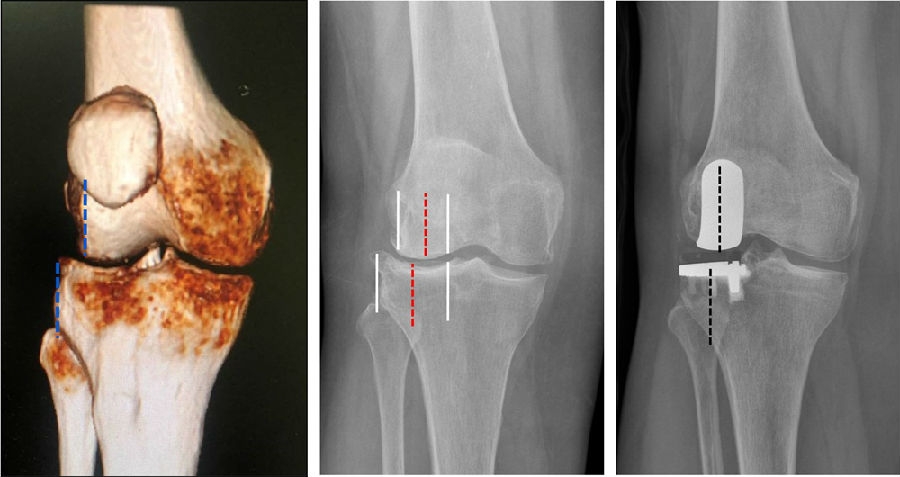

Case1:LUK治疗外侧间室OA

术前

术后